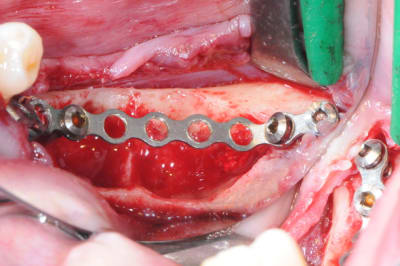

4-5-6-7 sciage de la mesh titane et positionnement in situ d'un bout à l'autre de l'arcade.

1-2

enfin, mise en place d'une membrane péricarde Jason de 30*50 (je crois)

3- j'ai profité de la stabilité de la mesh comme piquet de tente pour bourrer la cavité avec du MAXGRAFT (os humain)..

4-5- un peu de A-PRF (the king !)

6- le plus important des sutures hermétiques et une gencive immobile en fin d'intervention

7 les radios post-op